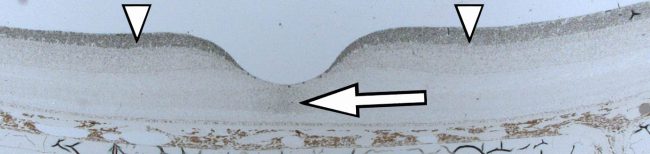

- Quantitative drug uptake, penetration, delivery and half life time studies in vivo in vitreous and retina.

- Routes of Drug Delivery

- Quantitative drug uptake, penetration, delivery and half life time studies in vivo in vitreous and retina.

- Routes of Drug Delivery